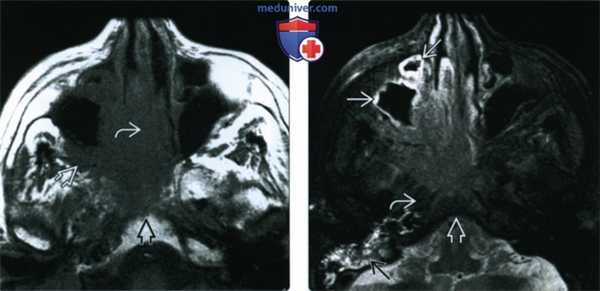

(Слева) При аксиальной МРТ Т1 определяется ПКР полости носа с вовлечением носовой перегородки, распространением кнаружи в крылонебную ямку и кзади в носоглотку, к основанию черепа.

(Справа) При аксиальной МРТ Т2 FS визуализируются края опухоли, отличной от утолщенной слизистой оболочки верхнечелюстной пазухи, превертебральных мышц и костного мозга ската с подавленным сигналом. Утолщение слизистой оболочки сосцевидного отростка связано с обструкцией евстахиевой трубы.

(Слева) При аксиальной МРТ Т1 определяется антральный ПКР очень большого размера с распространением в полость носа, подвисочную ямку и скат. Опухоль окружает левую внутреннюю сонную артерию но потоковое выпадение сигнала в ней сохранено.

(Справа) При аксиальной МРТ Т1 С+ FS определяется рак верхнечелюстной пазухи, равномерно накапливающий контраст, без явных зон некроза. Обратите внимание на инвазию ската и диффузную инфильтрацию жевательных мышц.